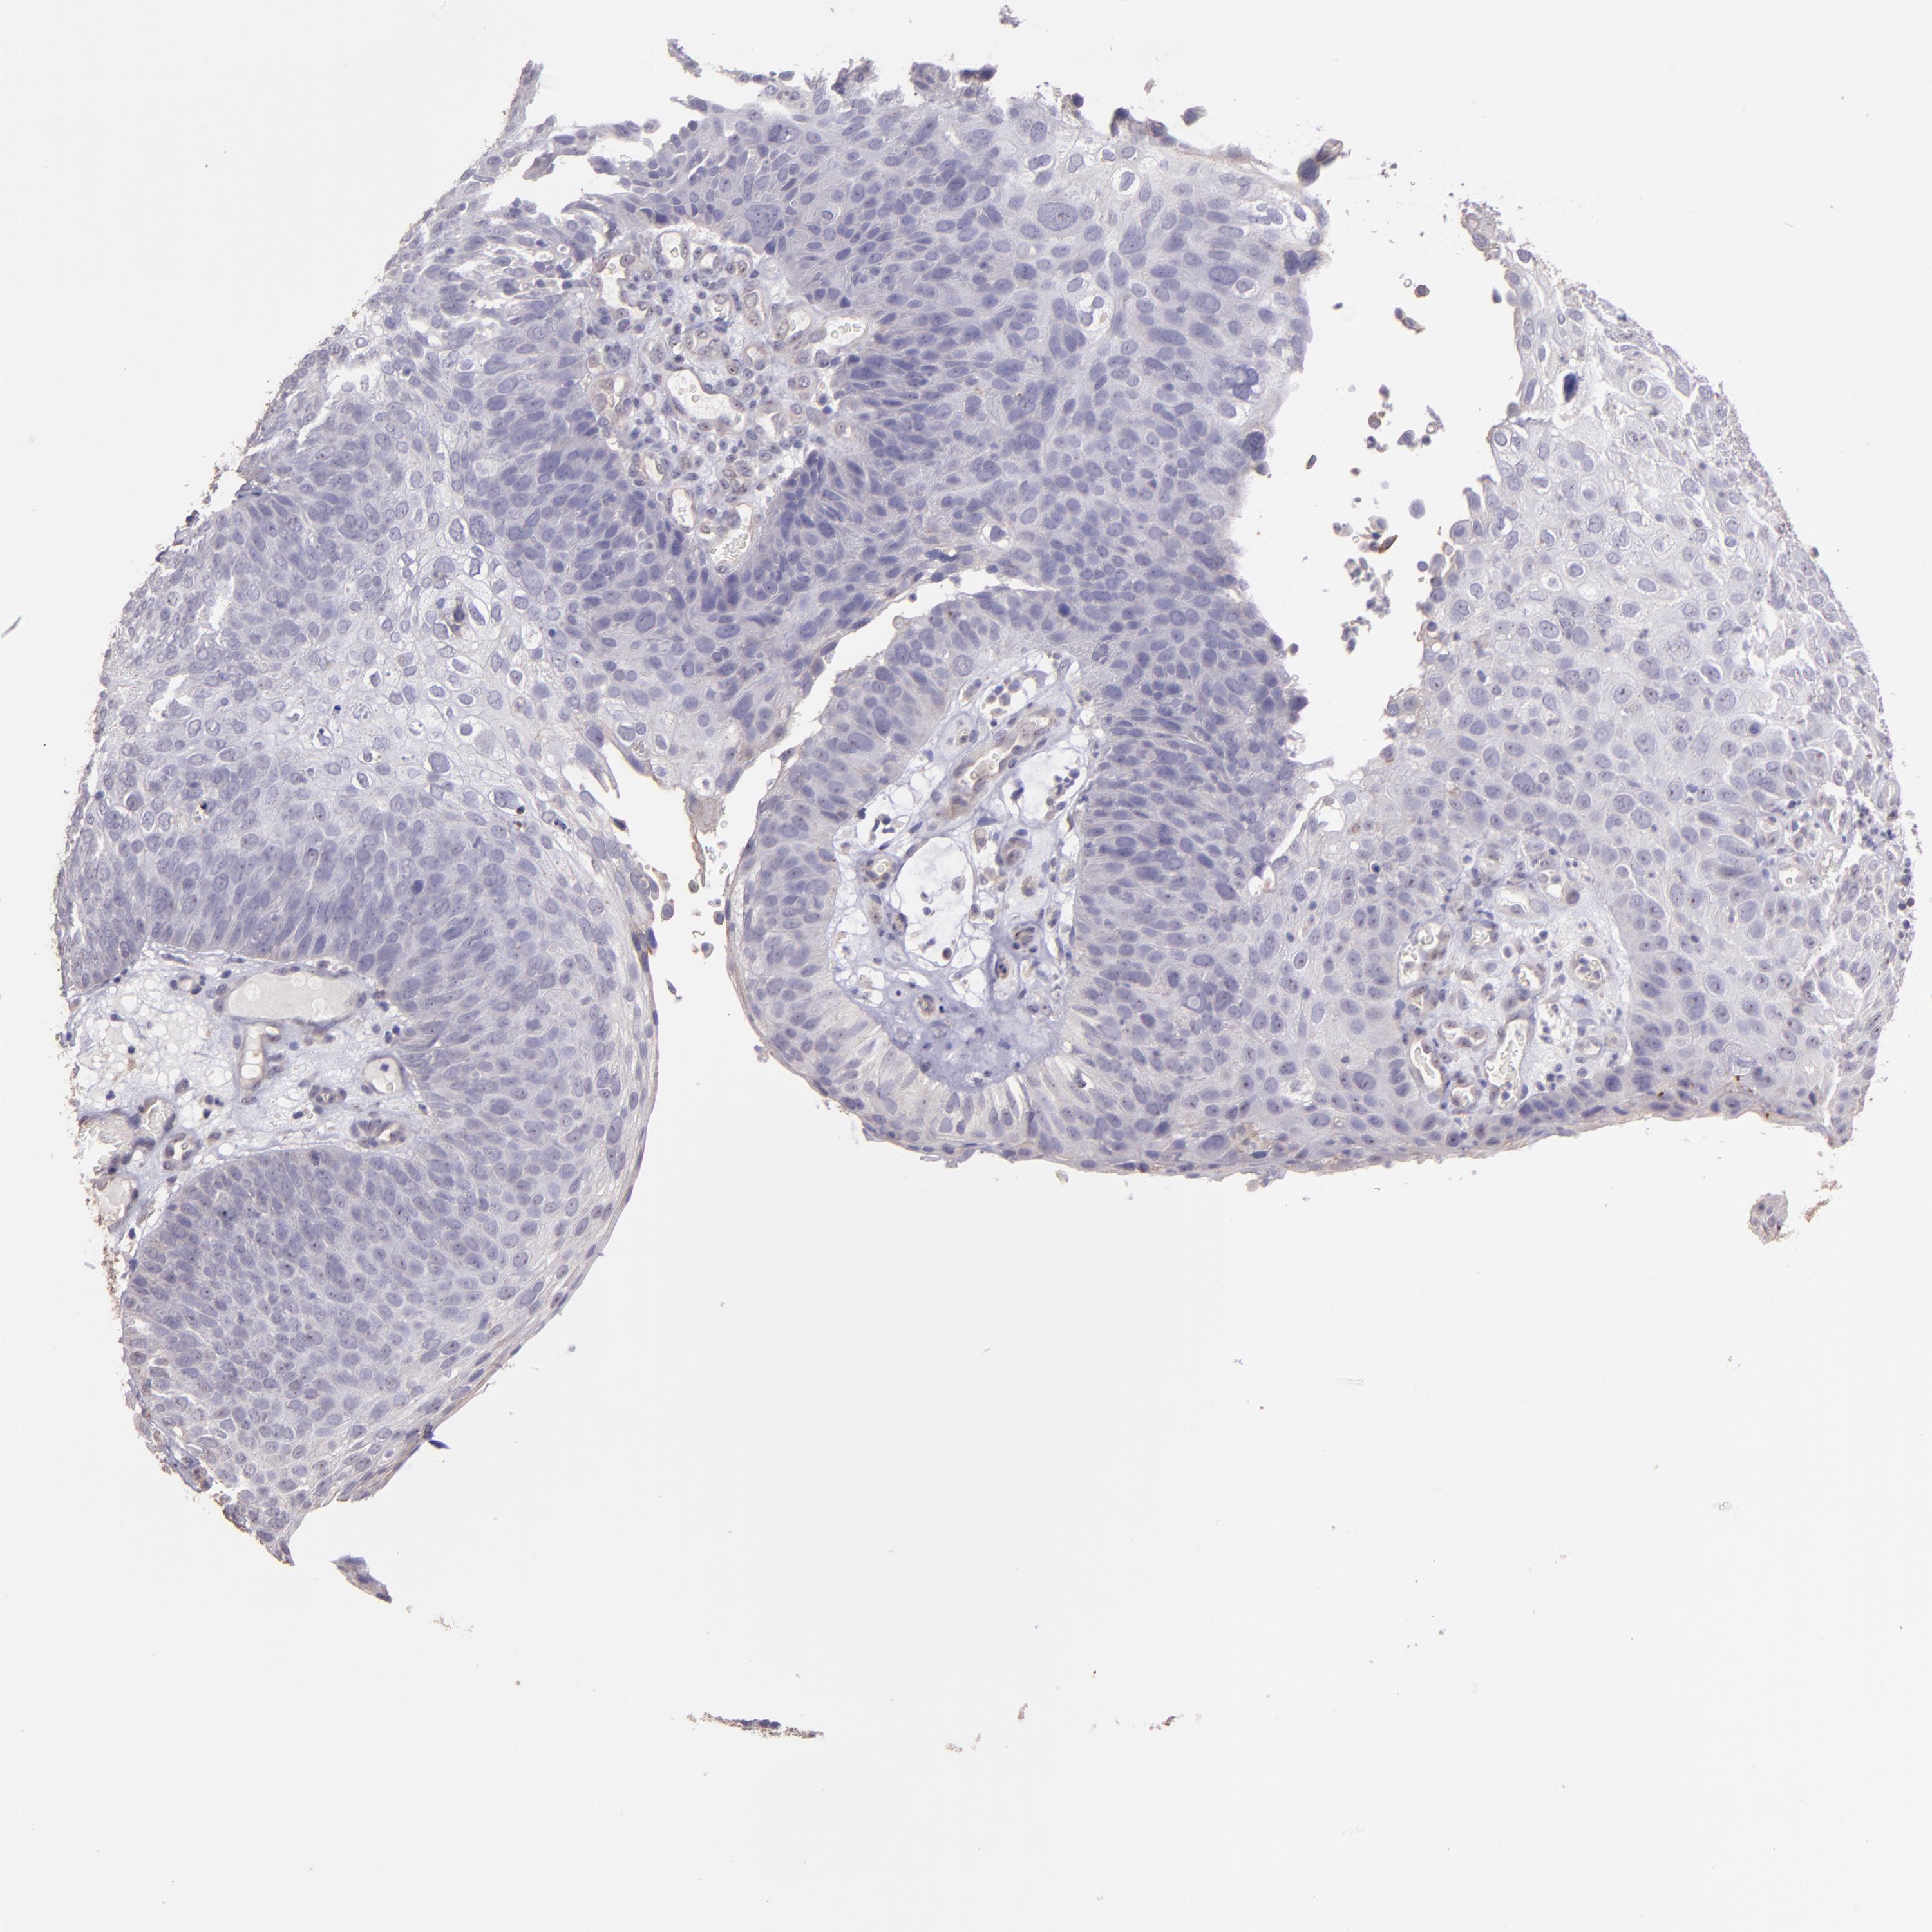

SKIN CANCER - Protein expressioni

A mouse-over function shows sample information and annotation data. Click on an image to view it in a full screen mode. Samples can be filtered based on level of antibody staining by selecting one or several of the following categories: high, medium, low and not detected. The assay and annotation is described here.

Antibody stainingi

Antibody staining in the annotated cell types in the current human tissue is reported as not detected, low, medium, or high, based on conventional immunohistochemistry profiling in selected tissues. This score is based on the combination of the staining intensity and fraction of stained cells.

Each image is clickable and will lead to virtual microscopy that enables deeper exploration of all samples and also displays staining intensity scores, fraction scores and subcellular localization as well as patient and tissue information for each sample.

Antibody HPA001667

Antibody CAB016724

Squamous cell carcinoma, NOS

Basal cell carcinoma

Squamous cell carcinoma, metastatic, NOS